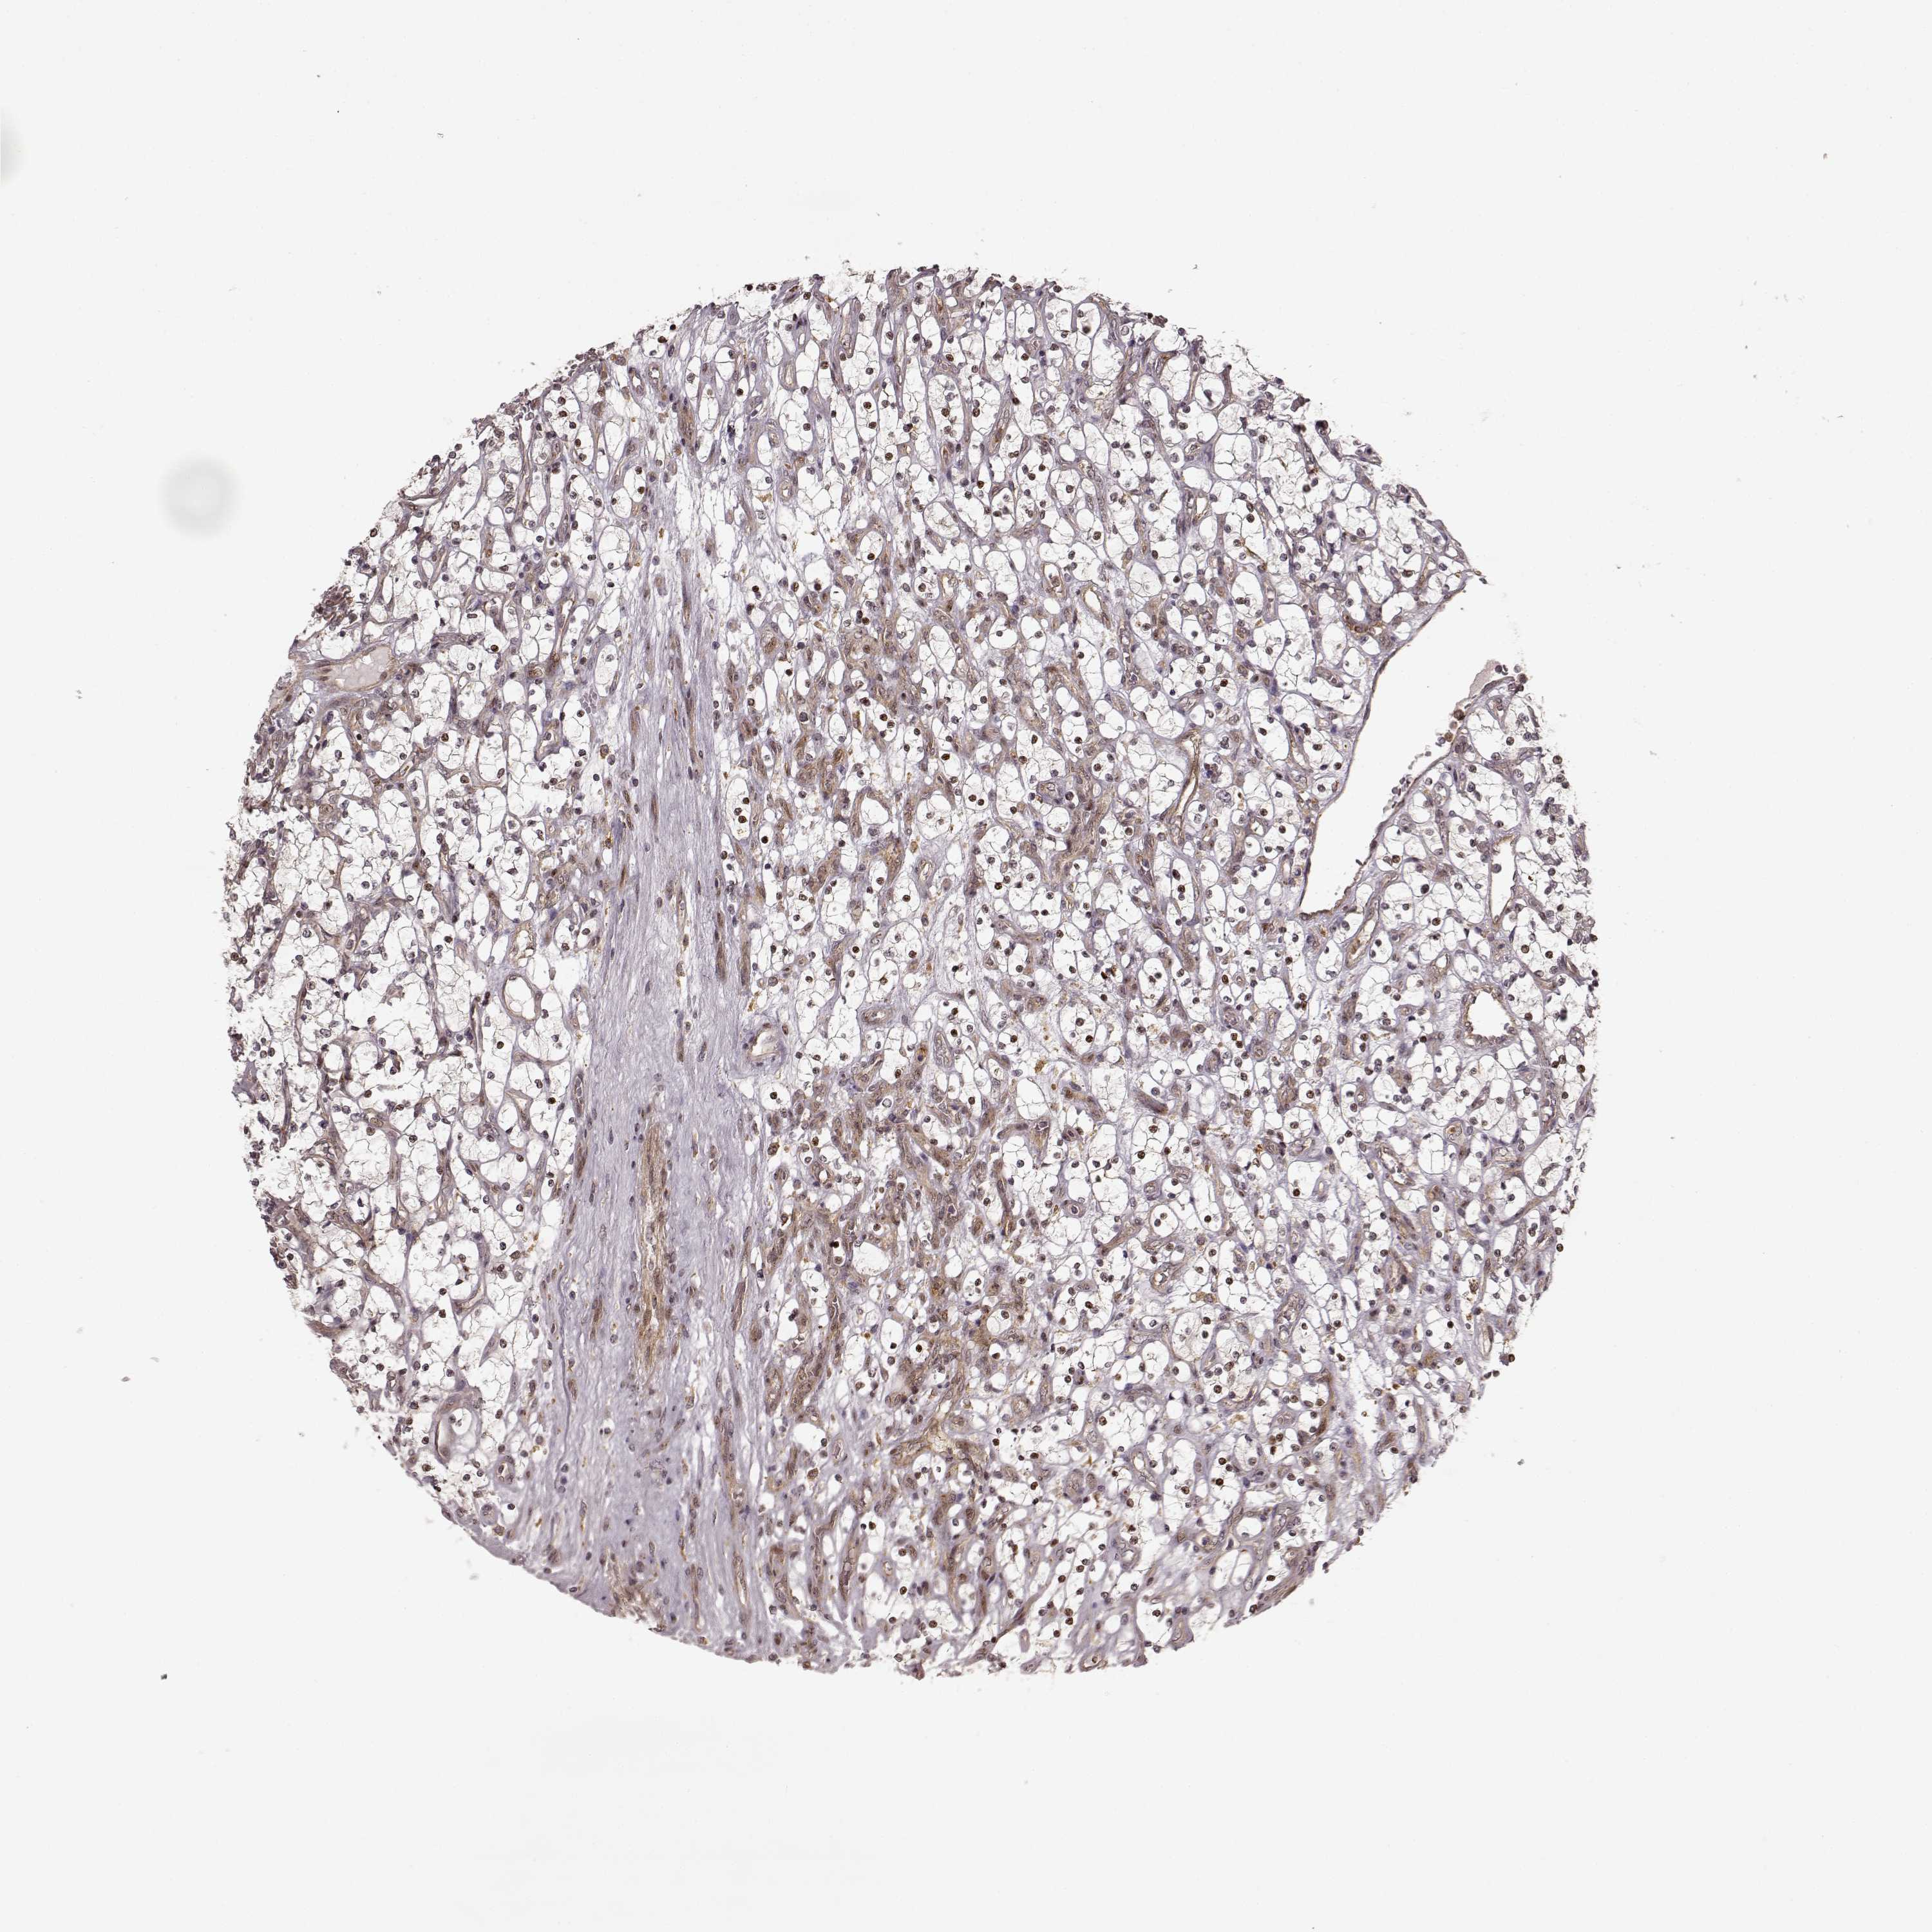

KIDNEY RENAL CLEAR CELL CARCINOMA (VALIDATION) - Interactive survival scatter ploti

The Survival Scatter plot shows the clinical status (i.e. dead or alive) for all individuals in the patient cohort, based on the same data that underlies the corresponding Kaplan-Meier plots. Patients that are alive at last time for follow-up are shown in blue and patients who have died during the study are shown in red.

The x-axis shows the expression levels (FPKM) of the investigated gene in the tumor tissue at the time of diagnosis. The y-axis shows the follow-up time after diagnosis (years). Both axes are complimented with kernel density curves demonstrating the data density over the axes. The top density plot shows the expression levels (FPKM) distribution among dead (red) and alive patients (blue). The right density plot shows the data density of the survived years of dead patients with high and low expression levels respectively, stratified using the cutoff indicated by the vertical dashed line through the Survival Scatter plot. This cutoff is automatically defined based on the FPKM cutoff that minimizes the p-score. The cutoff can be changed by dragging the vertical line or by entering a cutoff value in the square labeled "Current cut-off".

Under the Survival Scatter plot the p-score landscape (black curve; left axis) is shown together with dead median separation (red curve; right axis). Dead median separation is the difference in median mRNA expression between patients who have died with high and low expression, respectively. It is calculated as follows: median FPKM expression of dead patients with high expression - median FPKM expression of dead patients with low expression. This is intended to aid the user in visually exploring custom cutoffs and the associated p-scores and dead median separation.

Individual patient data is displayed and can be filtered by clicking on one or more of the category buttons on the top of the page. Categories describing expression level and patient information include: high, low, alive, dead, female, male and tumor stages. The scale of the x-axis can be toggled between linear and log-scale by clicking on the "x log" button. Mouse-over function shows TCGA ID, patient information and mRNA expression (FPKM) for each patient.

& Survival analysisi

Kaplan-Meier plots summarize results from analysis of correlation between mRNA expression level and patient survival. Patients were divided based on level of expression into one of the two groups "low" (under cut off) or "high" (over cut off). X-axis shows time for survival (years) and y-axis shows the probability of survival, where 1.0 corresponds to 100 percent.

SLC12A9 is not prognostic in Kidney Renal Clear Cell Carcinoma (validation)

Best expression cut offi

Based on the FPKM value of each gene, patients were classified into two groups and association between prognosis (survival) and gene expression (FPKM) was examined. The best expression cut-off refers the FPKM value that yields maximal difference with regard to survival between the two groups at the lowest log-rank P-value. Best expression cut-off was selected based on survival analysis .

When clicking on this number, the vertical dashed line indicating cut-off, the interactive survival plot, and the Kaplan-Meier curve will be adjusted to show results based on the best expression cut-off.

: 18.63

TCGA RNA samplesi

RNA-seq data is reported as average FPKM (number Fragments Per Kilobase of exon per Million reads), generated by the The Cancer Genome Atlas (TCGA) .

Normal distribution across the dataset is visualized with box plots, shown as median and 25th and 75th percentiles. Points are displayed as outliers if they are above or below 1.5 times the interquartile range. FPKM values of the individual samples are presented next to the box plot.

Average pTPM 16.2

Number of samples 100